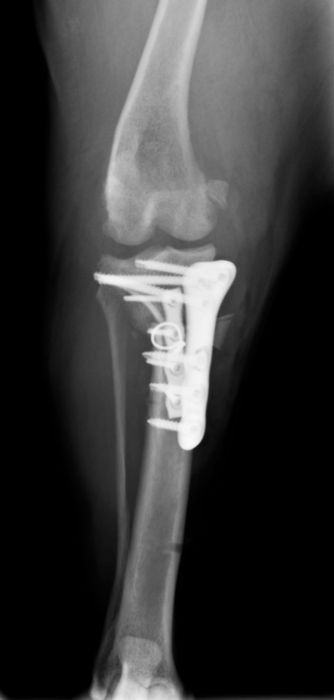

骨折治療について

動物も人間と同じように骨折や脱臼をします。

原因として交通事故などの大きな外力によるものもありますが、日本では小型犬が主体となっているため、ソファや抱っこしている所からの落下といった比較的小さな外力でも生じることが多くなっています。

骨折や脱臼の治療は、ギプスなどの処置のみで済むケースもありますが、ほとんどのケースは完全骨折や脱臼を生じますので、手術が必要となります。

当院における骨折治療は、動物のステータス、骨折の発生部位や分類などを考慮して「髄内ピン」「骨プレート」「創外固定器」を単独もしくは組み合わせて使用することで適当な固定力を得られるように施術しています。

●骨プレート

ステンレス製もしくはチタン製の金属の板(プレート)と骨ネジ(スクリュー)を使用して固定を行います。

●髄内ピンと骨プレートの併用(プレート-ロッド併用法)